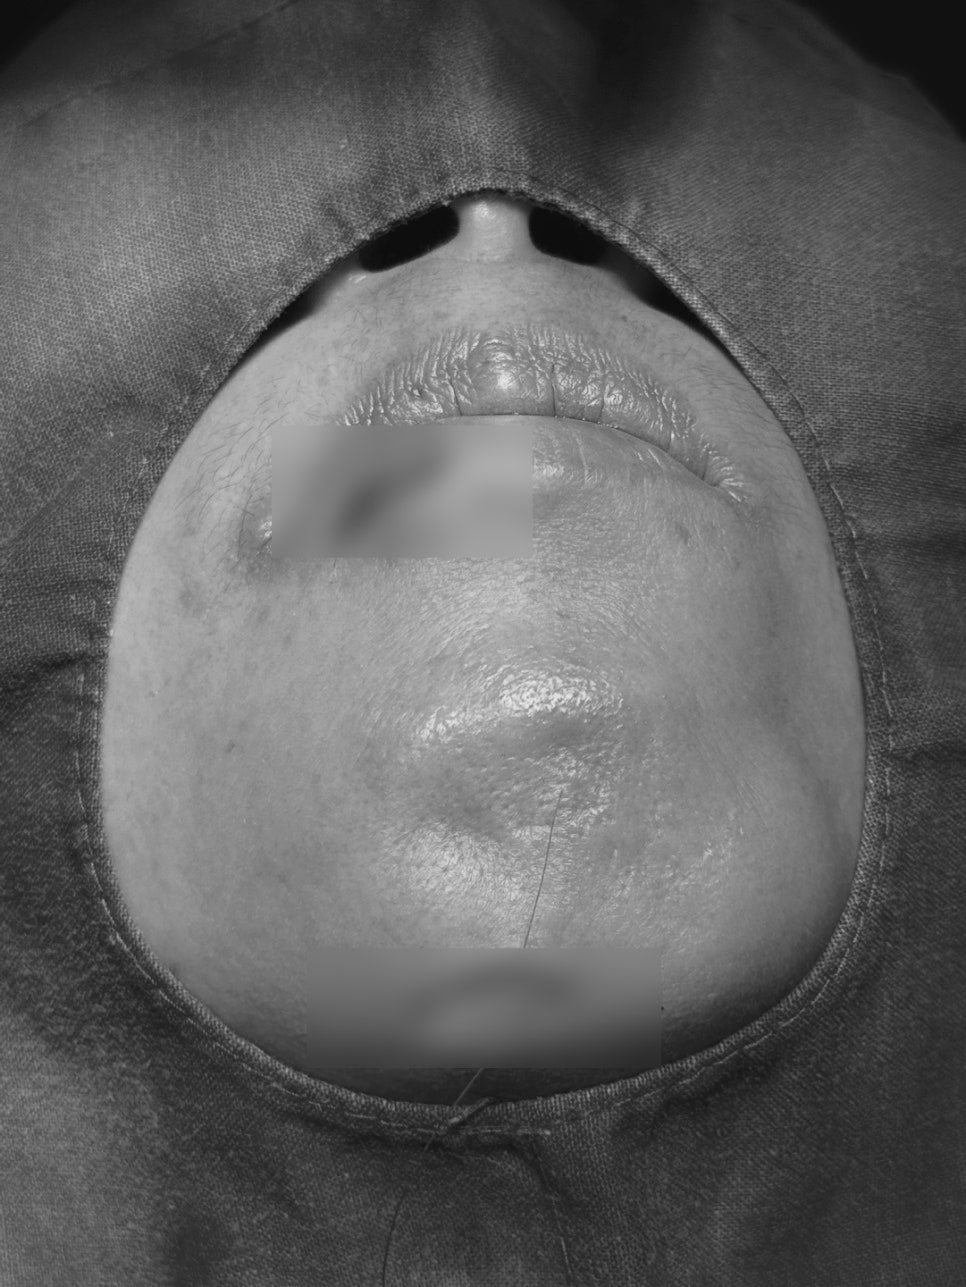

최근 서울오브치과병원에는

식사 중 어지럼증으로 넘어지며

입술과 잇몸이 크게 찢어지고,

앞니가 안쪽으로 밀려 들어간

50대 여성 환자분이 내원하셨습니다.

다발성 열상 봉합( 잇몸,입술,턱밑)

환자분은

잇몸 안쪽 열상,

입술 바깥쪽 근육층까지 깊은 열상

아래 턱 밑 열상이 있어

바깥·안쪽을 나눠 봉합술이 진행되었습니다.

(구강내 봉합 + 안면부 봉합)